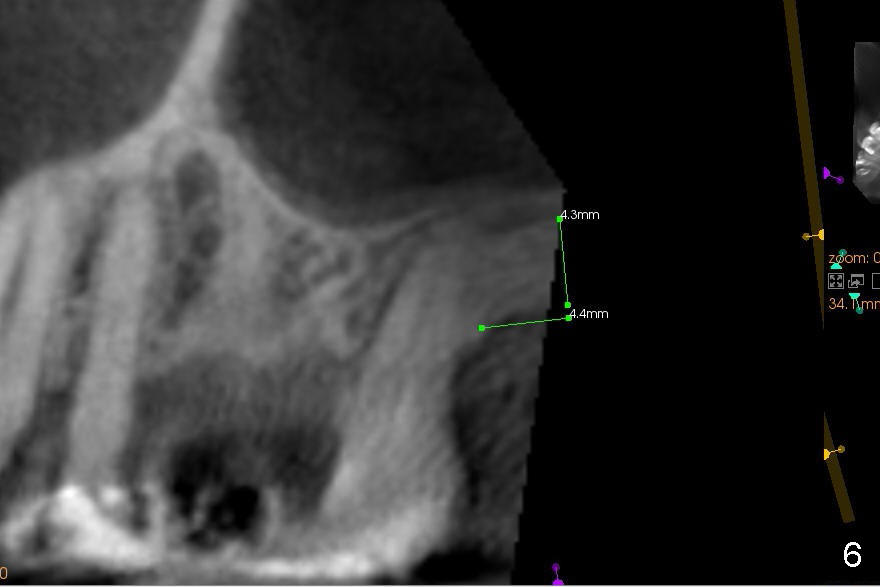

Anyway, a 1.6 mm pilot drill or 2 mm osteotome may be used to initiate osteotomy at the depth of 4-5 mm (Fig.3).  An explorer is used to check whether the sinus membrane has been reached or not.  As the diameter of bone expanders or osteotomes increases, the depth of the osteotomy increases (Fig.4), pushing the native bone into the sinus.  Each step check sinus membrane integrity by using an explorer or doing nose blowing test.  The implant can also push more bone upward when it is being placed (Fig.5).  Combined lateral and crestal sinus lift is not recommended in this case because of limited access.